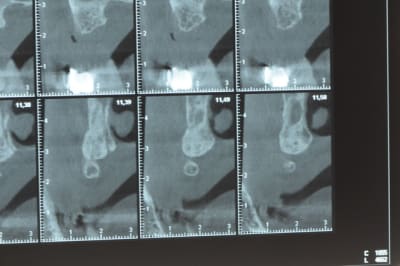

Une petite étude de ton cas D57

Sous réserves bien sur de voir l’animal en vrai

Les zones exploitables radiologiquement parlant:

Coupes implant

2,3 40100

4,96 35130 avec sinus lift mais difficile

5,25 35150

6,02 35130

6,78 35115 après réduction de hauteur de crête

7,26 35115 après réduction de hauteur de crête

8,51 35150

10,43 40115 ou 50115

11,10 40115

Ce qui nous fait 9 implants possible évidement avec un comblement de sinus on augmenterait encore les zones implantable mais ce n’est pas le but recherché, avec 8 (4+4) il doit être possible de faire une belle barre support de complet